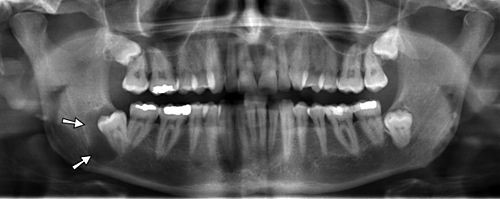

اگر درد یا تورم در فک خود دارید یا متوجه تغییر در ظاهر خود مانند وجود توده در فک یا جابجایی دندان ها شده اید، به پزشک مراجعه کنید. این ممکن است نشانه کیست، تومور یا یک بیماری دندانی جداگانه باشد که پزشک شما می تواند آن را درمان کند. مراجعه منظم به دندانپزشک بسیار مهم است. عکسبرداری معمولی از دندان ها می تواند علائم کیست یا تومور را زمانی که هنوز کوچک است و علائمی ایجاد نمی کند، نشان دهد.